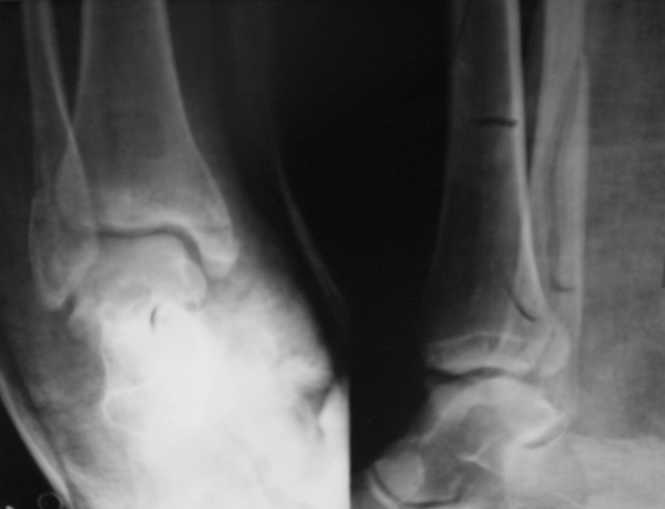

Перелом лодыжекКонтрольные рентгенограмы сделаны с нарушением укладок для стандартных проекций. Переделайте рентгенснимки и догда можно будет о чем-то иметь дискуcсию.

Рентгенограммы не сделаны в строго боковой и передне-задней проекциях.

Но и здесь видно, что внутренняя лодыжка "висит" - это говорит об интерпозиции. Выполняйте открытую репозицию и металлостеосинтез.

Можно сделать прямую с внутренней ротацией в 20 гр - еще лучше будет видно. Внутренняя лодыжка на боковом снимке не так уж плохо стоит. В любом случае - надо сделать нормальные снимки.

Вопрос к автору сообщения - эти лодыжки в задней гипсовой лонгете, судя по снимкам, или показалось?

Вот рентгенконтроль на 7-е сутки после репозиции.